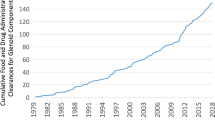

In shoulders with severe glenohumeral arthritis, the preoperative pathologic features commonly include glenoid retroversion and posterior decentering of the humeral head relative to the glenoid face [9, 45, 46, 53, 54]. Surgical treatment of these pathologic features can be a challenge; in their presence glenoid failure attributable to “rocking horse” loosening is a concern [17, 23, 28, 50, 55, 56]. Some authors suggest that glenoid components should be inserted in 15° or less retroversion to avoid inferior outcomes [3, 6, 10, 17, 47]. Several methods to address increased glenoid retroversion have been described [5, 21, 46], including overreaming the anterior “high side” of the glenoid (Fig. 1) [14, 59], posterior glenoid bone grafting [16, 34, 43], posteriorly augmented glenoid components [40, 44, 49, 64], and reverse total shoulder arthroplasty (TSA) [33].